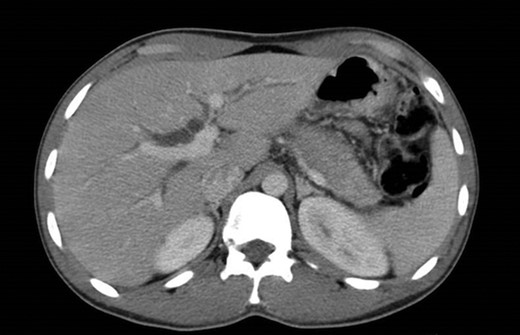

The abdominal exam revealed a soft, non-distended, non-tender abdomen, without any palpable masses, organomegalies or lymphadenopaties. Blood chemistry showed a cholestatic pattern: bilirubin 6.61 mg/dl, alkaline phosphatase 434 U/l, gamma-glutamyl transpeptidase 374 U/l, alanine transaminase 542 U/l and aspartate transaminase 228 U/l. Lipase, amylase and complete blood count showed regular values. Abdominal ultrasound revealed dilatation of the intra and extrahepatic bile ducts and the pancreas was enlarged and hypoechoic, compatible with inflammation. CT scan was performed to discard a neoplastic obstruction and confirmed an intrahepatic biliary ductal dilatation (Fig. 1) and a dilatation of the distal bile duct with no luminal lesions (Fig. 2).

Pancreatic CT scan. General dilatation of the intrahepatic biliary tree and terminal common bile duct.